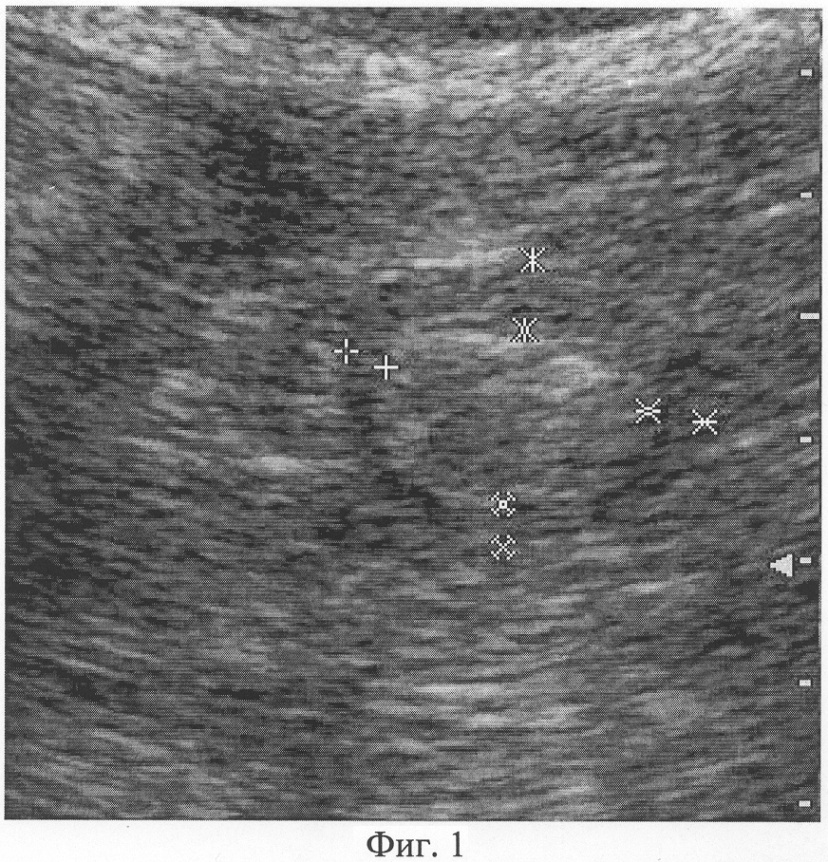

При фиксации изображения в момент полного раскрытия просвета гастродуоденального перехода осуществляют измерение толщины его мышечного слоя, который визуализируется как широкая гипоэхогенная полоска с четкими контурами, расположенная по периферии ультразвукового поперечного среза. Причем измерение толщины производят по передней, верхней, задней и нижней стенкам гастродуоденального перехода, как показано на Фиг.1. Аналогичным образом проводят измерение толщины мышечного слоя гастродуоденального перехода в фазу максимального его смыкания, как показано на Фиг.2.

Фиг.1. Сканограмма (режим серой шкалы, поперечная проекция) гастродуоленального перехода: фаза полного раскрытия просвета, толщина мышечного слоя R1=4,8 мм, R2=5,9 мм, R3=3,4 мм, R4=3,6 мм.